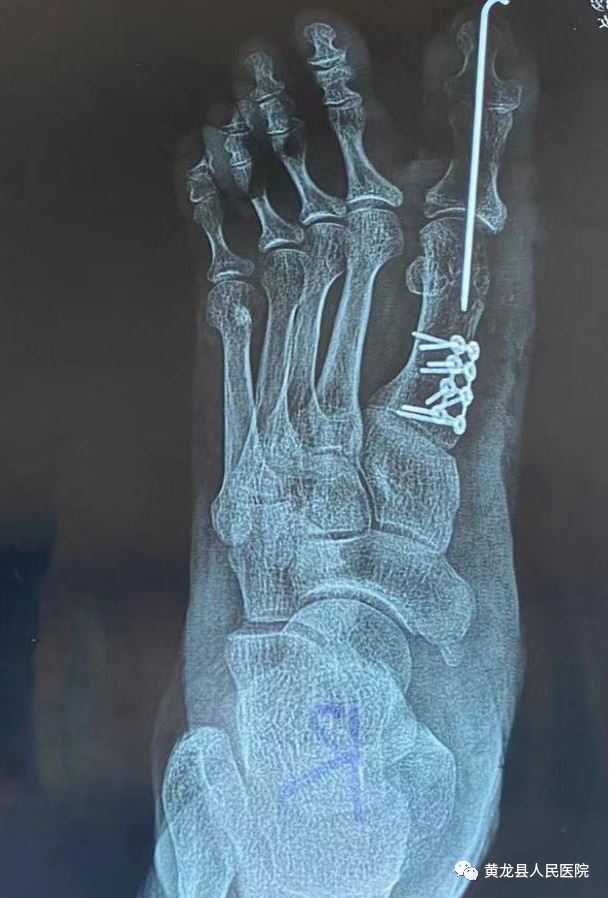

术前X线 术后X线

以上大家看到的影像图片,是一位58岁的女性患者,由于双足踇趾畸形3年余,剧烈疼痛导致穿鞋及活动严重受限。3年前,患者出现双足踇趾向外偏斜,当时畸形不严重,踇趾内侧稍红肿,未予诊治,1年前右足踇趾内侧疼痛明显,活动后疼痛加剧,只有休息后才能稍缓解。患者于1月11日来到黄龙县人民医院外科就诊,经过外科主任方继荣详细询问病史及仔细体格检查后,将患者收治入院治疗。结合患者病情,多方考虑需手术效果最佳,告知患者及家属得到同意。术前,考虑到患者年龄稍微偏大,手术有风险。方继荣带领外科医师对手术风险做了充分评估,对手术方案进行多次讨论,制定了详细周密的手术方案,最终于1月14日上午顺利进行手术。方继荣主刀,在外科医师及手麻科积极配合下,仅用不到1小时,手术顺利完成,达到了术前预期效果,经过手术治疗后,患者脚部成功恢复了美丽的外观,患者及家属对手术效果表示非常满意,向医务人员多次表示感谢。